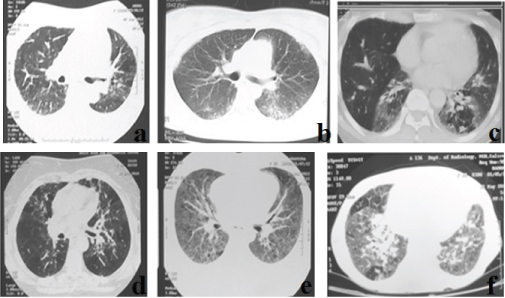

After clinicoradiological assessment of 169 DPLD patients, we had 66 patients in whom the diagnosis was inconclusive. These included 42 female (64%) and 24 male (36%) patients. Of the total 33 patients were above 60 years (50%), 27 patients were in age group 30–59 years (41%) and 6 patients were below the age 30 (9%). The major patterns in HRCT lung sections included ground glassing/consolidation in 45 (68%), reticular shadows in 20 (30%), and septal thickening in 25 (37.8%). Some images also showed nodules in 10 (15%), cysts in 2 (3%), mosaic attenuation in 9 (13.6%) and honey combing in around 22% (predominant upper zonal). If the honey combing fit the criteria for a definite UIP, they were excluded [2]. Few of the representative HRCT lung images are shown in [Table/Fig-1].

Few of the representative HRCT lung sections.

a-f-: Images a and d shows areas of patchy ground glassing and mosaic attenuation; b shows peripheral subpleural patchy ground glassing and consolidation; c shows ground glassing with contracted lower lobes; e shows bilateral diffuse ground glass opacities; f shows bilateral ground glassing with peribronchovascular consolidation in the right lower lobe and patchy areas of mosaic attenuation.